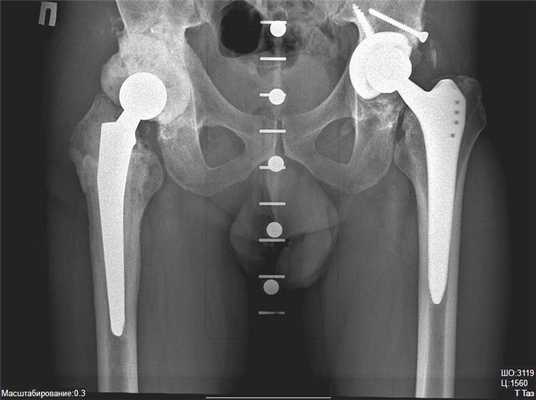

Противопоказания к замене сустава абсолютные и относительные: почему не допускают к операции

Эндопротезами называют искусственно произведенные приспособления, предназначенные для замены определенных внутренних органов человека и полноценно выполняющие их функцию. Так протезы тазобедренных суставов позволяют пациентам, перенесшим операцию, выполнять весь тот комплекс движений, который выполняют люди без патологий в этой области. Кроме того, протезирование избавляет от болей и дискомфорта, благодаря чему становиться возможным возвращение к полноценной активной жизни.

Такой вид вмешательства может быть показан во многих случаях: при заболеваниях опорно-двигательного аппарата или после перелома шейки бедра, если его двигательная функция была частично или полностью утрачена.

Несмотря на все результаты, которых достигают при помощи операции, назначают ее не всегда. Дело в том, что она имеет множество противопоказаний и факторов риска.

Основные (абсолютные) противопоказания

Абсолютными противопоказаниями считаются те, наличие которых однозначно препятствует проведению операции. В данных ситуациях она либо бесполезна, либо существует высокая вероятность усугубления уже имеющихся патологий.

К таким случаям относят:

- Клинические состояния, при которых пациент не имеет способности самостоятельно передвигаться, но причина этого не связана с дефектом тазобедренного сустава. Проводить процедуру нецелесообразно, так как возобновить двигательную активность человека она не поможет.

- Хронические заболевания в стадии декомпенсации (этап, при котором приспособительные механизмы какого-либо органа исчерпали свои возможности, и он больше не может функционировать нормально из-за присутствующего дефекта). Препятствием к хирургическому вмешательству может быть наличие:

- технической невозможности установки протеза.

Относительные противопоказания

Относительными противопоказаниями считаются факторы, которые не препятствуют установке протеза, но являются поводом проведения для более детальных исследований и рассмотрения возможности операции в индивидуальном порядке.

К таким показаниям принято относить случаи:

Современные разработки в области медицины и ортопедии позволяют проводить уникальные операции даже при наличии этих факторов. Со временем многие особенности и вовсе перестают причислять к противопоказаниям.

Главное, что определяет возможность протезирования – соотношение риска и пользы. Если патология исключает возможность нормального передвижения, а риск минимален – операция, вероятнее всего, будет проведена. При этом обо всех возможных последствиях пациента и его близких родственников предупреждают заранее, так их решение тоже имеет очень большое значение, и оно должно быть осознанным и обдуманным.